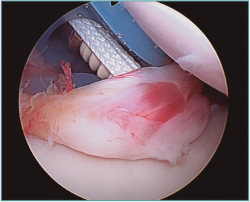

Siempre que se pueda, el ligamento se colocará por fuera de la cápsula, incluso por debajo del labrum si existiera (Figura 7).

Figura 7. Visión articular del ligamento con el tornillo, insertado por debajo del labrum.